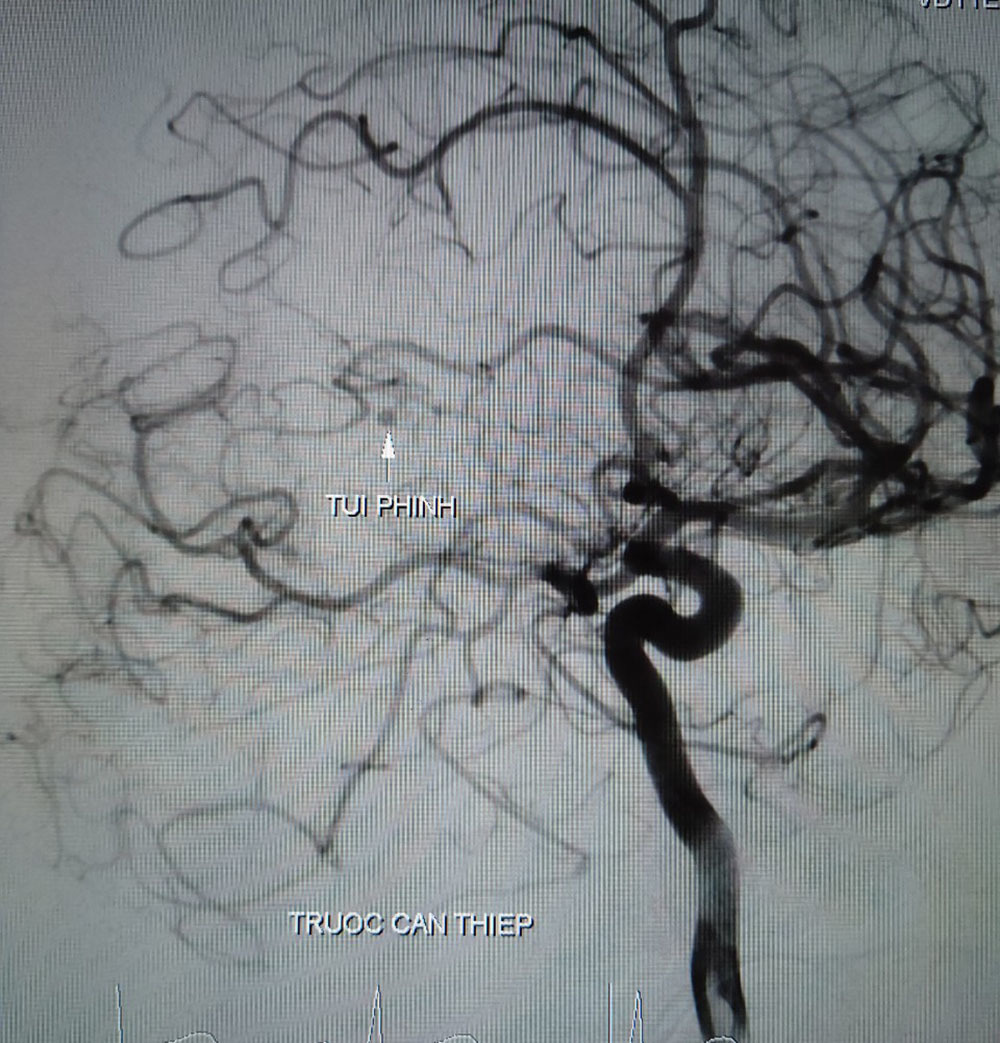

| Hình ảnh túi phình mạch não của bệnh nhân T. trước khi can thiệp |

Qua hội chẩn, bác sĩ quyết định thực hiện chụp mạch máu kỹ thuật số xóa nền. Kết quả cho thấy, có búi dị dạng động tĩnh mạch não vị trí gần não thất bên ở bên trái.

Bác sĩ đã tiến hành nút dị dạng và bảo toàn các nhánh mạch máu lành. Sau khi nút dị dạng thành công, bệnh nhân được tiếp tục phẫu thuật để dẫn lưu máu và dịch trong não ra ngoài làm giảm áp lực trong sọ.